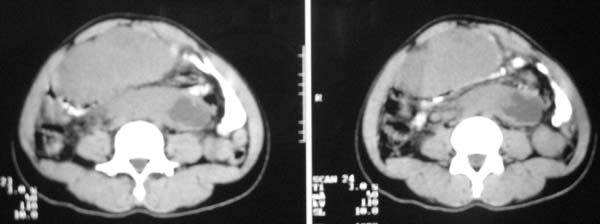

以下是引用zjzjr在2007-9-27 22:20:00的发言:[br]肠腔受推移,未见明显扩张及液平,所以考虑是肠外病灶, 间叶源性肿瘤?脂肪瘤?建议增强。

以下是引用guzhongliangddd在2007-9-27 23:21:00的发言:[br][br]与肠内高密度相同,病灶应该没有钙化,我认为首先考虑是间叶组织的良性肿瘤。建议楼主做后重建观察。中线区域大血管旁未见确切增大淋巴结。病灶对肠道只是推移关系。

以下是引用余辉在2007-9-27 22:24:00的发言:[br]暂考虑肠道间质来源肿瘤如小肠平滑肌肉瘤/瘤可能,应该增强